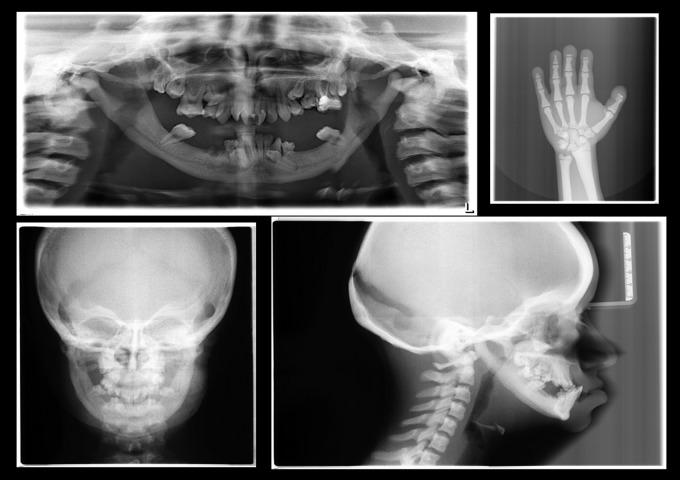

The aim of this article is to present intra- and extra-oral and cephalometric findings of three patients with a rare disease: the pycnodysostosis. Two cases had skeletal Class III malocclusion due to maxillary retrognathia and one had bimaxillary retrusion with Class I relationship. Total circular crossbite, increased gonial angle and vertical facial proportions, deep-narrow palates and retruded upper lip were found in all cases. Maxillary expansion, face mask treatment or/and orthognathic surgery are treatment alternatives, considering the growth and development. Bone fragility and the risk of osteomyelitis after extractions should be considered in such cases before orthodontic treatment and orthognatic surgery.

本文旨在呈现三名患有罕见疾病——致密性骨发育不全症患者的口内、口外及头影测量结果。两例患者因上颌后缩出现骨性III类错牙合,一例患者为双颌后缩,呈I类关系。所有病例均存在全牙列反牙合、下颌角增大及垂直面部比例异常、腭部深而窄以及上唇后缩的情况。考虑到生长发育因素,上颌扩弓、面罩治疗或/和正颌手术是可供选择的治疗方法。在此类病例中,正畸治疗和正颌手术前应考虑骨脆性以及拔牙后发生骨髓炎的风险。